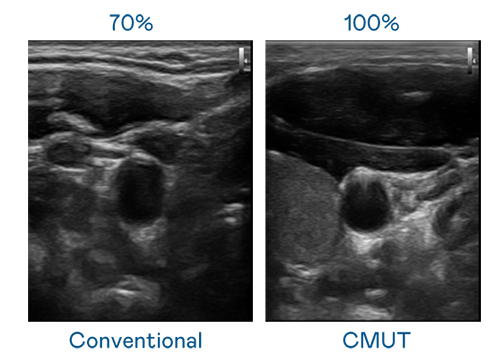

CMUT 技术是一种用电容式微机电元件来产生超音波讯号的技术。与传统 PZT 压电式技术相比,CMUT 频宽增加 30%,更宽频的超音波讯号让影像解析度大幅提升,是实现高影像品质医疗超音波扫描、促进精准医疗发展的关键技术。

超音波影像的解析度高低,首先取决于探头能发出的讯号频宽。狮子会 CMUT 可提供高清晰的超音波讯号,提供高频宽、高灵敏度、影像纹理细节更高的超音波影像,协助医护人员缩短影像判读时间及利用精准的医疗影像进行诊断。